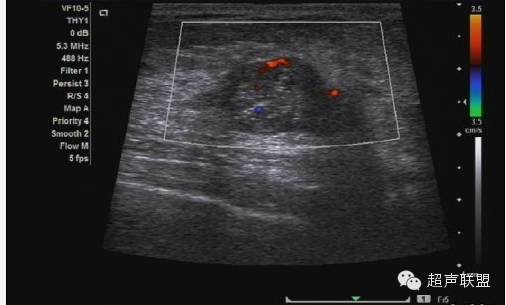

使用造影剂的缺点在于造价高,并需要静脉注射。而且,灵敏度更高的多普勒仪器的出现使得血流信号的增强已不像过去那么重要。图4显示,在移植入肝脏中的实验性肿块上运用造影剂后,组织的对比度增强。类似的增强是否也适用于乳腺组织亟待研究。